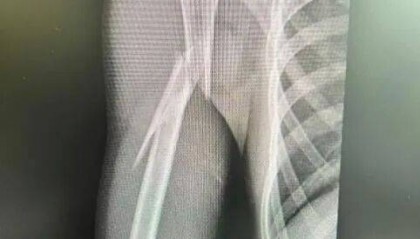

10岁男孩遭遇洗衣机“陷阱”,右臂粉碎性骨折!医生提醒

洗衣机还在运转 孩子就把手伸进正在转动的机器里取衣服 结果右臂被卷入 造成右肱骨干粉碎性骨折 据新民...